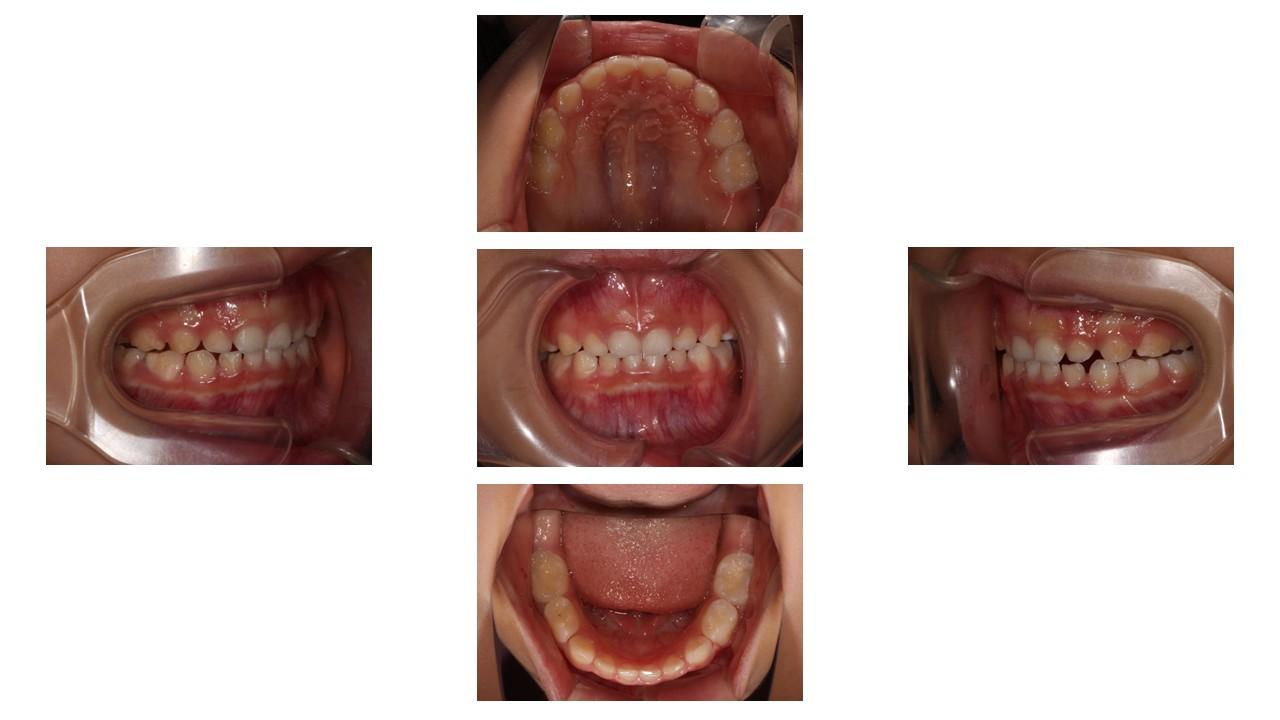

「過蓋咬合」とは、上下の歯の噛み合わせが異常に深い状態のことです。

<正常な噛み合わせ> 上下の歯を自然に噛み合わせたとき、上の前歯は下の前歯を約2〜3ミリ(歯の頭の3分の1程度)覆っているのが理想的です。

<過蓋咬合> 上下の歯を噛み合わせたとき、上の前歯が下の前歯を深く覆いかぶさってしまい、下の前歯がほとんど見えない状態です。場合によっては、下の前歯の先端が上の歯茎に当たってしまうほど深く噛み込んでいることもあります。

【過蓋咬合を治す必要がある理由】過蓋咬合は一見、見た目上大きな問題がないように感じられるかもしれませんが、放置するとお口の健康や全身に様々な悪影響を及ぼす可能性があります。